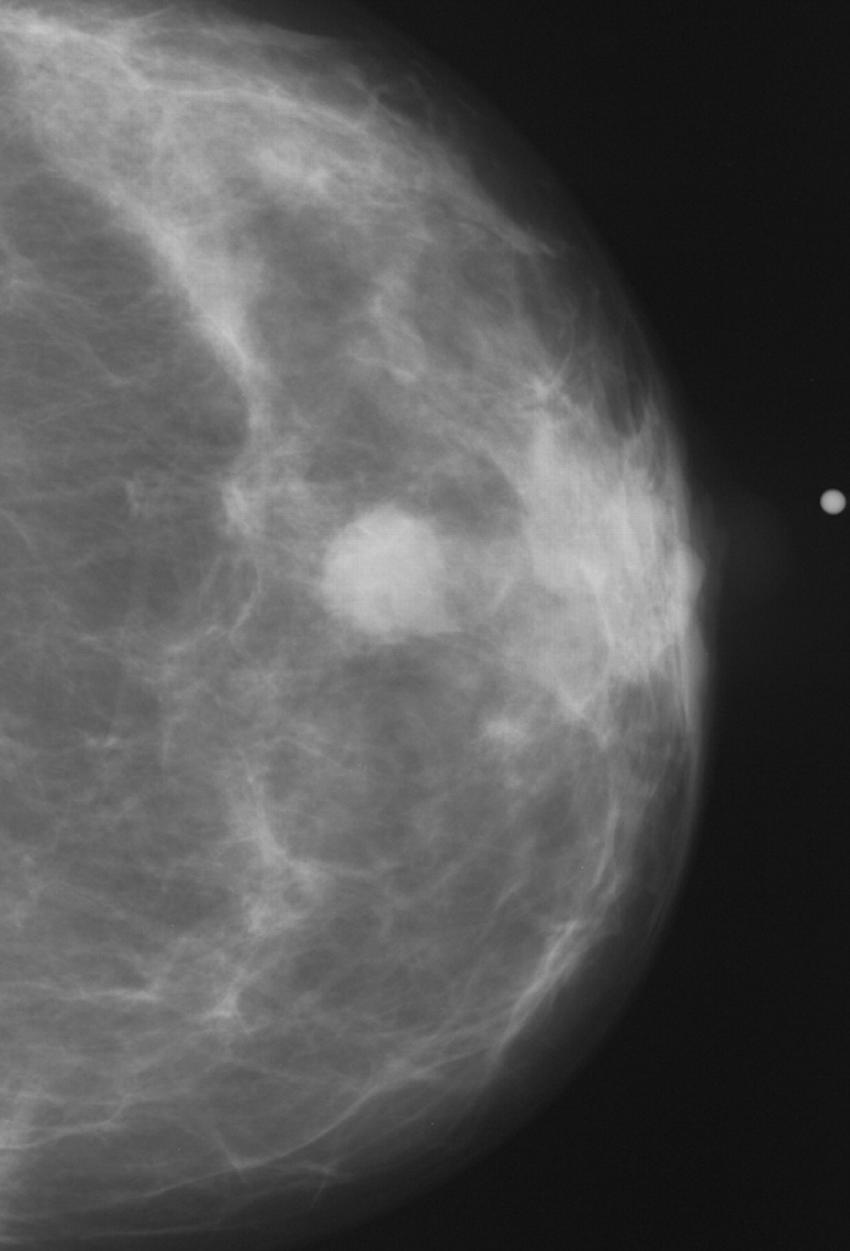

Figure 8. Abnormal mammogram.